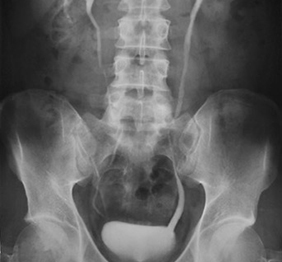

Urografie

Urografia intravenoasa (UIV) este un examen radiologic care ofera o imagine detaliata a rinichiului si a tractului urinar inferior.